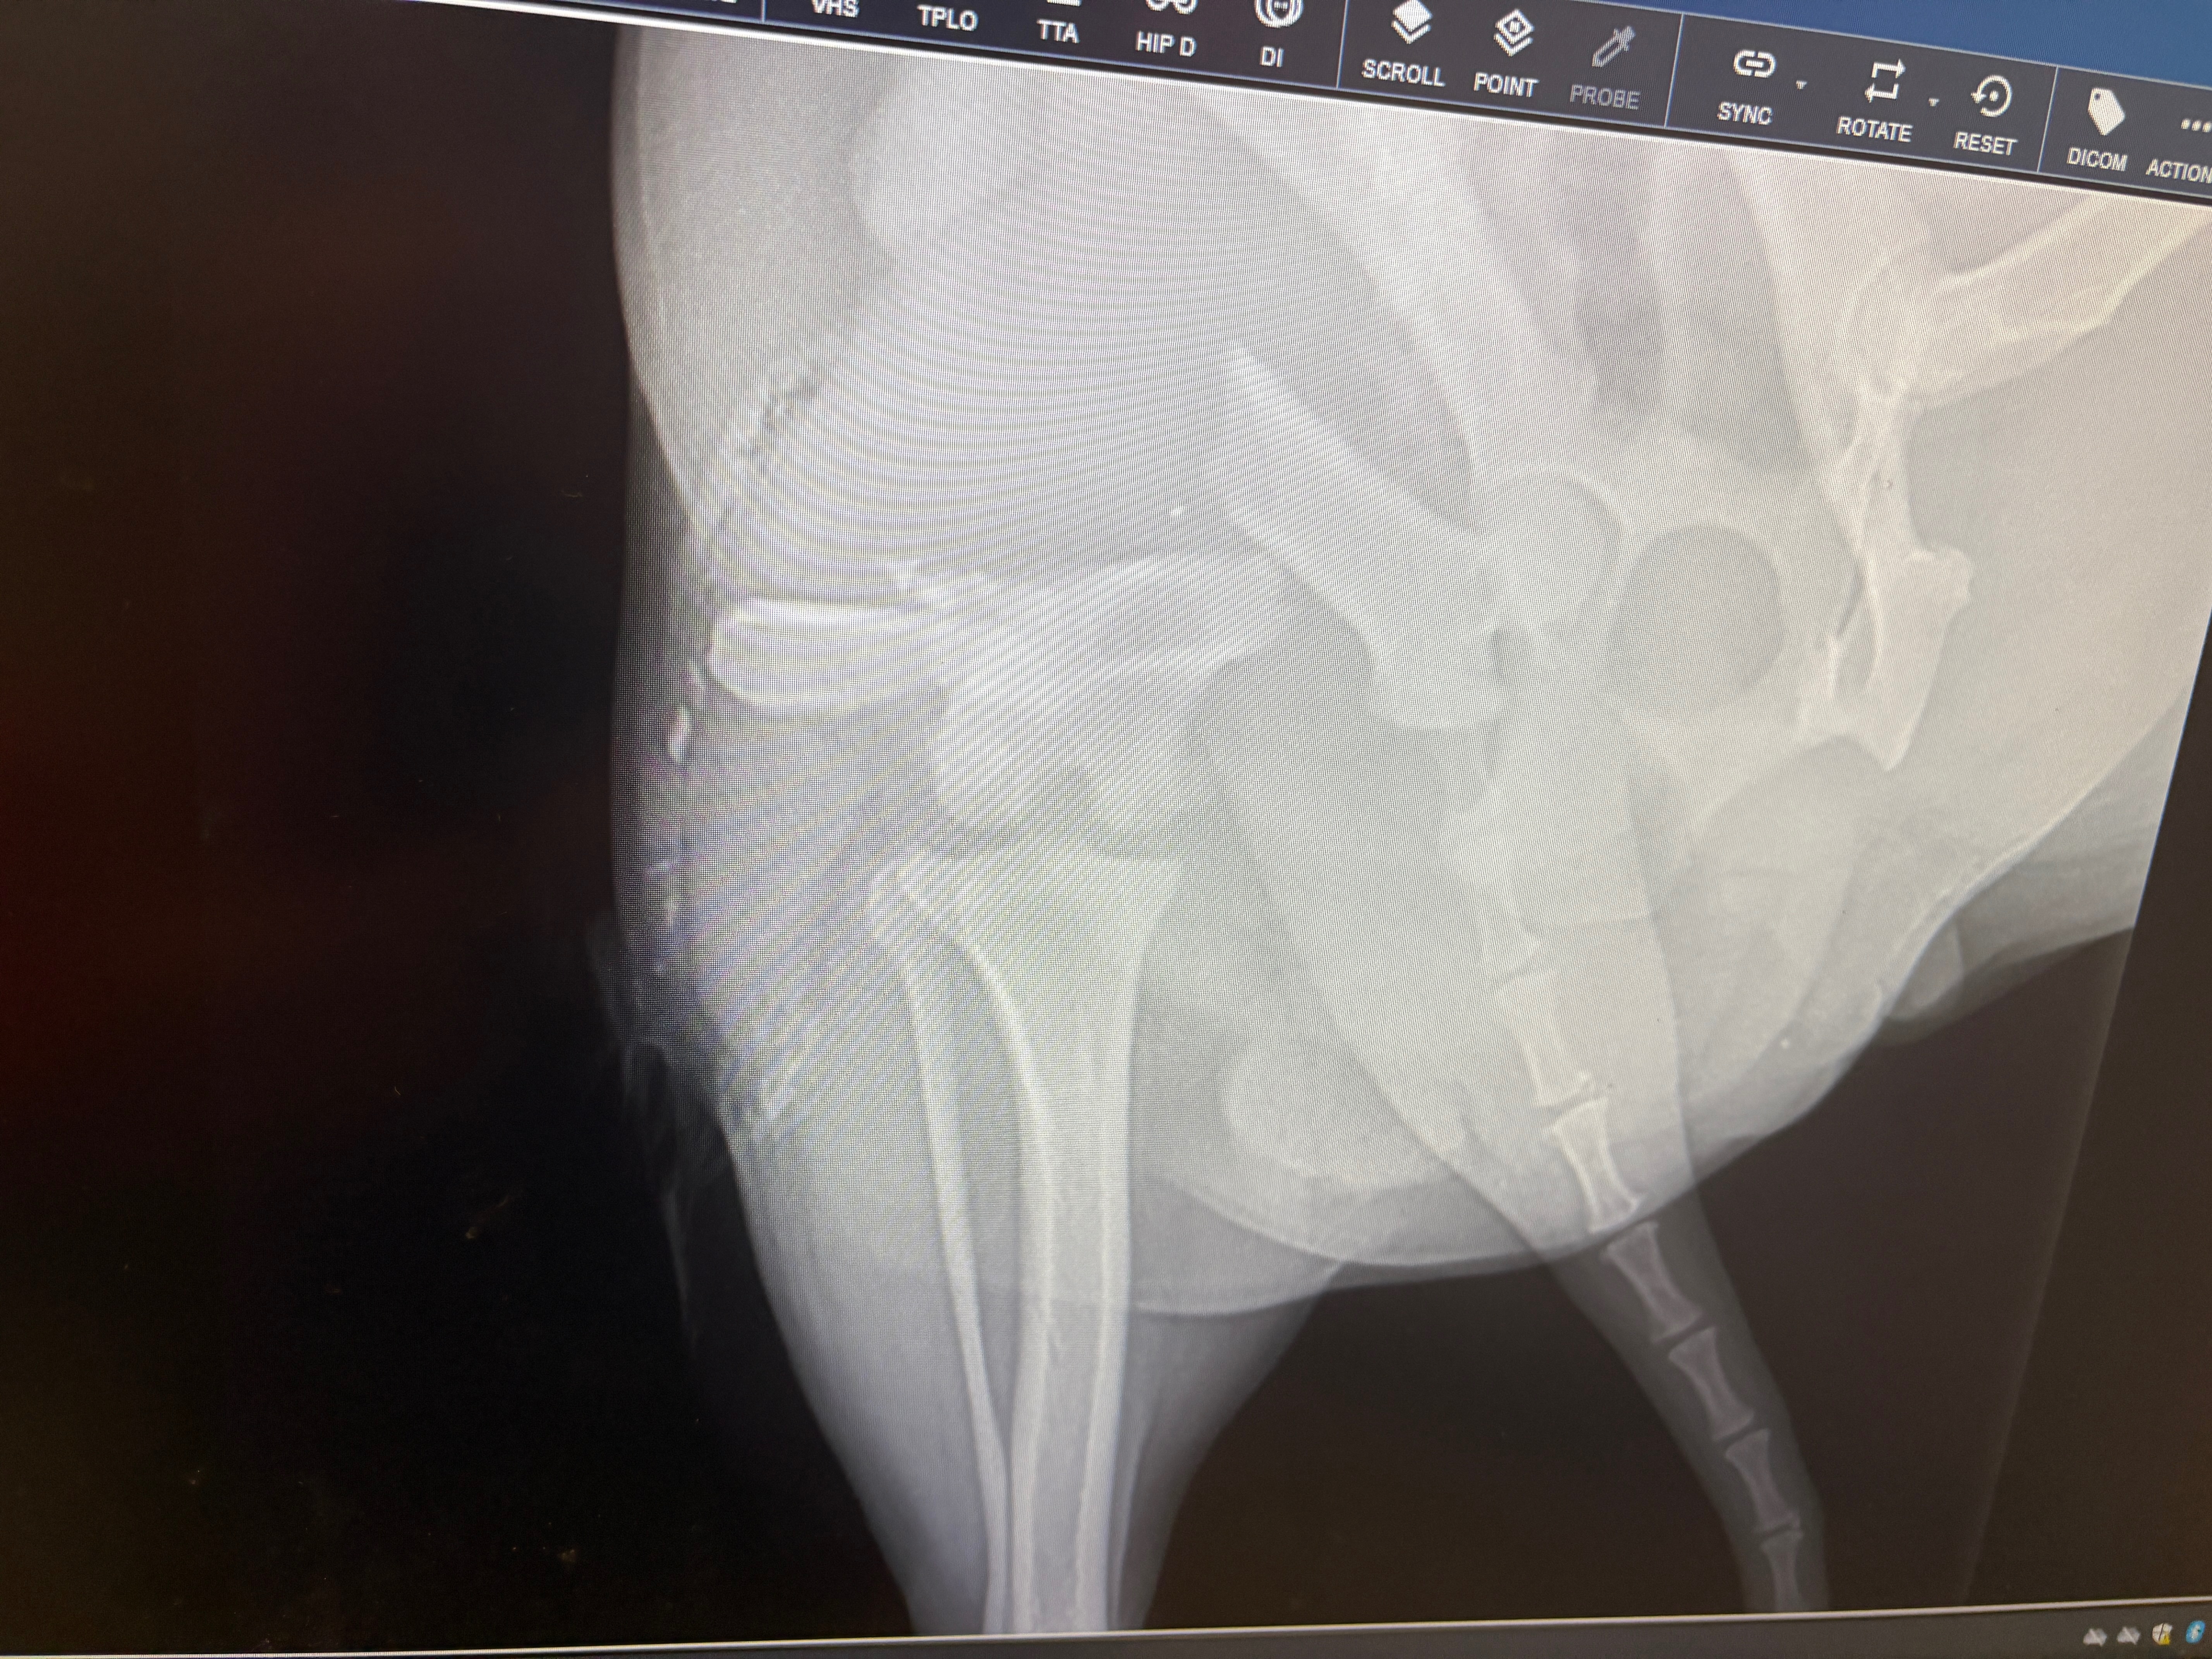

Our sweet girl now has a compound fractured femur and needs urgent surgery to save her leg and allow her to walk again. The veterinary team says the procedure will cost $10,894 — an amount far beyond what we can afford. Without this surgery, Aries faces unimaginable pain and the possibility of losing her leg.